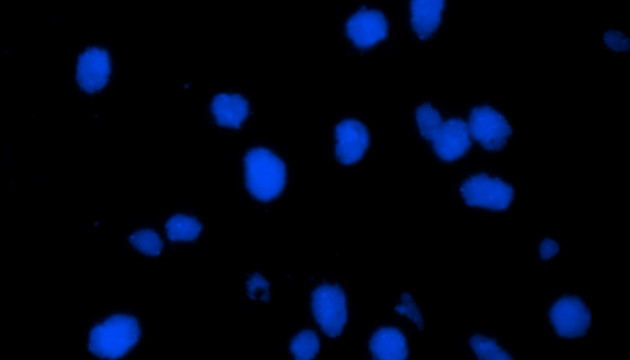

熒光原位雜交(Fluorescence In Situ Hybridization,F(xiàn)ISH)是臨床病理檢測(cè)中廣泛運(yùn)用的一種分子細(xì)胞遺傳學(xué)診斷技術(shù),其原理是用熒光染料直接或間接標(biāo)記的DNA核酸探針與待測(cè)樣本中的DNA核酸序列按照堿基互補(bǔ)配對(duì)的原則進(jìn)行雜交,然后通過(guò)熒光顯微鏡觀察熒光信號(hào)位置、數(shù)量等來(lái)判斷待測(cè)序列的缺失、擴(kuò)增及易位等情況。其高分辨率、直接反映異常細(xì)胞比例、快速簡(jiǎn)便的特點(diǎn),使其成為臨床檢測(cè)、預(yù)后評(píng)估及用藥指導(dǎo)的重要工具。

FISH技術(shù)面臨熒光弱、背景噪聲、多通道疊加等難點(diǎn)。為了保障熒光信號(hào)強(qiáng)度,一般需要用到研究級(jí)熒光顯微鏡,半復(fù)消色差或以上的物鏡,以及高功率的LED熒光光源或汞燈光源;為了去除背景噪聲,一般需要搭配高截止深度的濾光片和高靈敏度相機(jī);多通道疊加時(shí)要提取紅綠信號(hào)點(diǎn),然后放到藍(lán)色DAPI信號(hào)上,處理需要相當(dāng)?shù)募记伞?